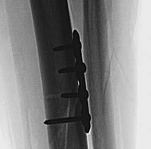

With the articular surface reconstituted, the surgeon's focus shifts to bridging the complex metaphyseal-diaphyseal dissociation. A pre-contoured anatomical locking plate is slid submuscularly or subcutaneously along the diaphysis using a MIPPO technique. The plate is positioned on the anterolateral or medial surface, depending on the preoperative plan and soft tissue constraints.

The distal portion of the plate is secured to the reconstructed articular block. It is imperative that the distal locking screws are placed parallel to the joint space, forming a rigid subchondral raft that supports the articular cartilage. Fluoroscopy is utilized extensively to ensure no screws have penetrated the joint. Once the distal block is secured to the plate, the diaphyseal segment is aligned. Length, alignment, and rotation are restored using manual traction or the femoral distractor. The proximal portion of the plate is then secured to the diaphysis using a combination of non-locking screws (to pull the bone to the plate) and locking screws (to create a fixed-angle construct). The working length of the plate is maximized by leaving several screw holes empty over the zone of comminution, promoting secondary bone healing.